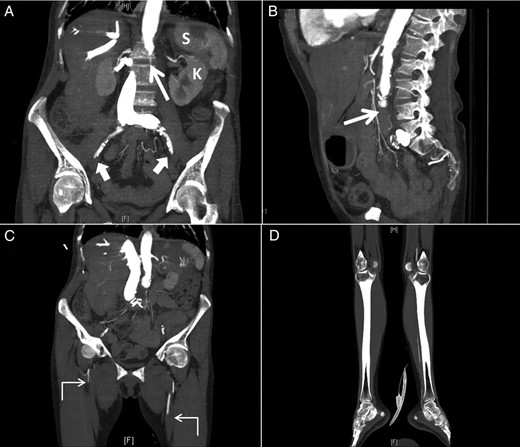

TTE 4-chamber view during systole (A) and diastole (B) showing a large LAM attached to the interatrial septum and obstructing diastolic filling of the left ventricle and follow-up four-chamber view during systole (C) and diastole (D) showing a marked reduction in the size of the LAM (LA, left atrium; LV, left ventricle; RA, right atrium; RV, right ventricle).

The next morning after her coronary angiogram, the patient suddenly showed signs of confusion and began to experience slurred speech and left-sided facial droop with left-sided hemiplegia. She was intubated to protect the airway and was sent for an urgent computed tomography (CT) scan of the head, which revealed a hyperdense minute clot lodged at the right internal carotid artery bifurcation. Accordingly, tissue plasminogen activator thrombolytic therapy was initiated. A repeat TTE showed that the mass was markedly decreased in size (2.1 × 0.9 cm) compared with a previous study, likely due to embolization (Fig. 1C and D).